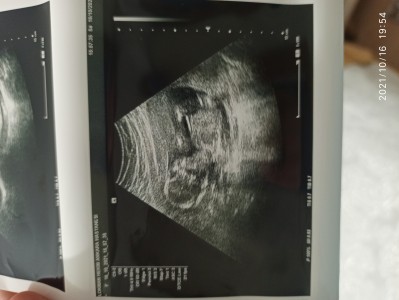

Cinsiyettahminisizcenedir

Kizlar sizce cinsiyeti nedir şuan 17 haftaligiz

17

Kız sanki sağlıkla gelsin

Bakar bakmaz erkek hissettim hayurli evlat olsun inşallah

Bende bakar bakmaz erkek hissettim canm hayırlı evlat olsun inşallah